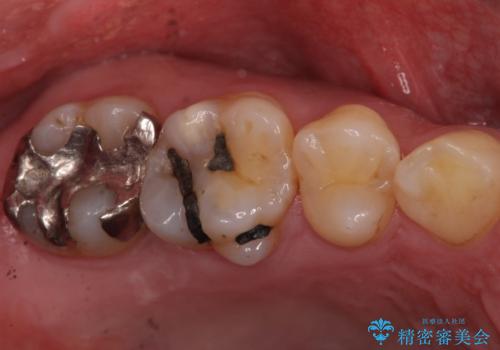

- 昔、治療された銀歯が気にな流ということを主訴で来院された患者様です。

銀歯を外し、虫歯治療を行い、セラミックインレーにて治療しました。

銀歯を除去し、虫歯をとって、セラミックインレーにて治療を行いました。